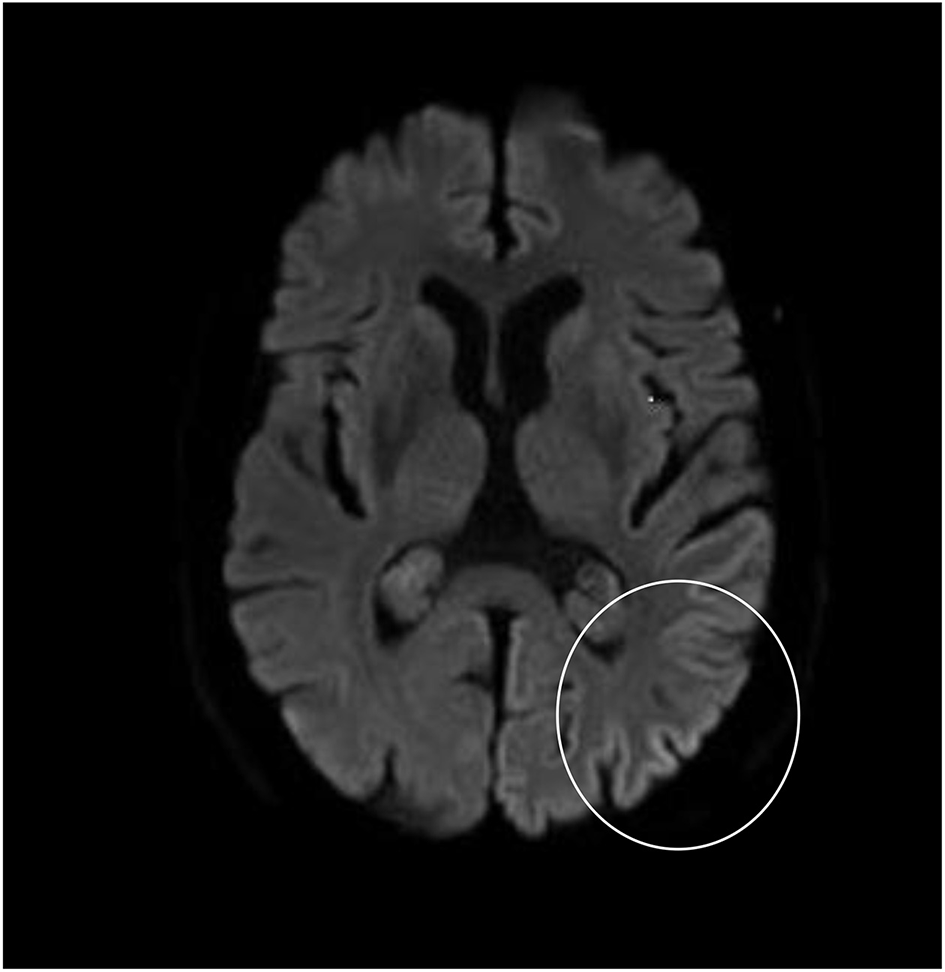

Although neurological examination, routine blood testing, and a head MRI (including diffusion-weighted imaging, DWI) showed no abnormalities, our patient became increasingly forgetful and disoriented, and was subsequently admitted to our hospital. There we saw a previously eloquent man who now suffered from aphasia, ataxia, myoclonic jerks, and a rapidly progressive dementia. A second head MRI showed low apparent diffusion coefficient (ADC) values and increased DWI-signaling in the left parieto-occipital cortex, characteristic of a cortical ribbon sign (Figure 1), while the electroencephalogram showed periodic sharp-wave complexes (PSWC) over the same area (Figure 2). The MRI with presence of 14-3-3 proteins and elevated tau protein in the cerebrospinal fluid supported the diagnosis of probable sporadic Creutzfeldt-Jakob disease (CJD), notably the Heidenhain variant. We excluded other possible causes, including auto-immune disorders, infections, malignancies, toxic and metabolic encephalopathies, and other neurodegenerative diseases (notably posterior cortical atrophy and dementia with Lewy bodies). We did not carry out genetic testing because the family history was negative for neurodegenerative disease, CJD in particular. Unfortunately there were no therapeutic options. In conformity with his wishes, our patient was discharged home, where he died within 2 months after his visual symptoms had begun. We were unable to obtain autopsy consent.

Figure 1. High signal intensity of the left parieto-occipital cortex on diffusion-weighted MRI (DWI; b = 1,000).